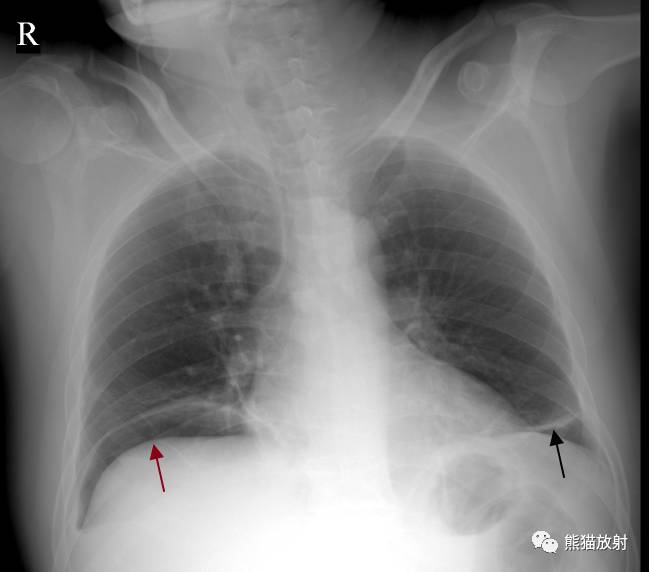

↓ 右侧气胸(肺压缩约70%),右肺上叶肺段不张(尖端指向肺门)

↓ 结肠癌术后,左下肺盘状肺不张,右侧膈下游离气体